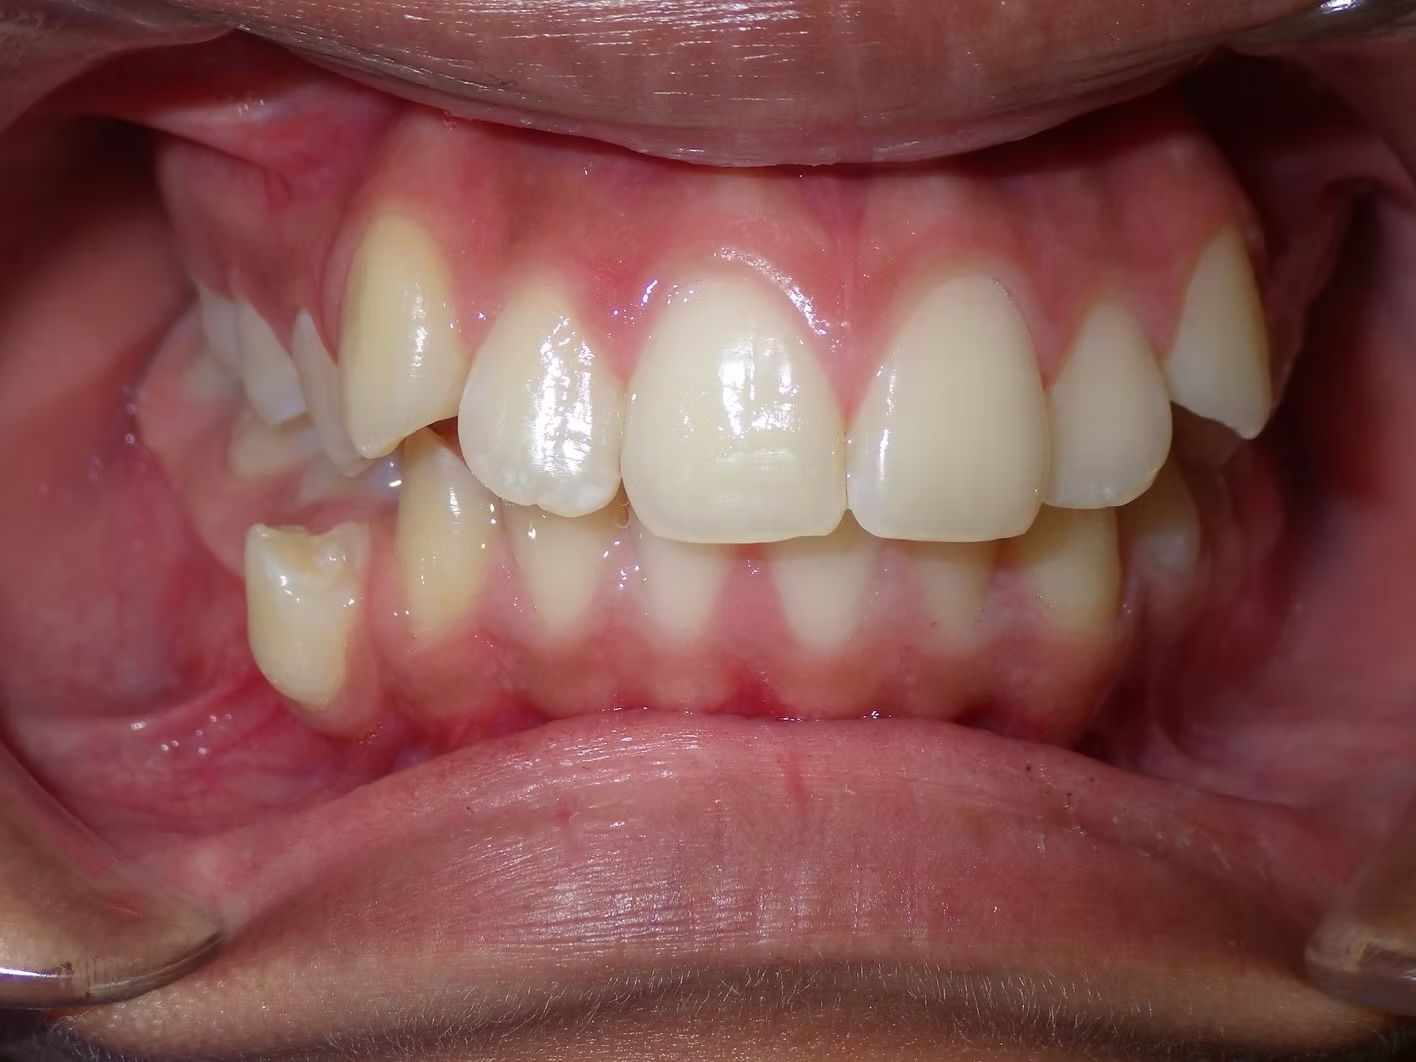

BRIANNA

Brianna's lower left 1st premolar was completely in a brodie bite (outside the normal arch) and her top and bottom teeth were very crowded. Dr. Freedman corrected her bite and crowding without removing any teeth.